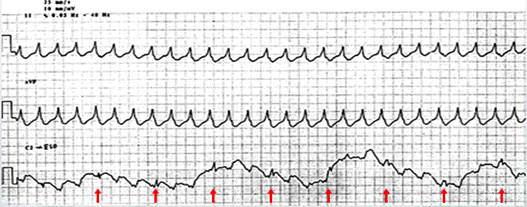

食管心电图鉴别 宽QRS波心动过速常因体表心电图P波不易识别而无法鉴别,食管心电图可显示清晰P波,易于宽QRS波心动过速的鉴别。

病例1

宽QRS波心动过速。体表心电图无法识别有否P波,而食管心电图可清晰显示P波,且呈现为房室分离,提示本例宽QRS波心动过速为室速。